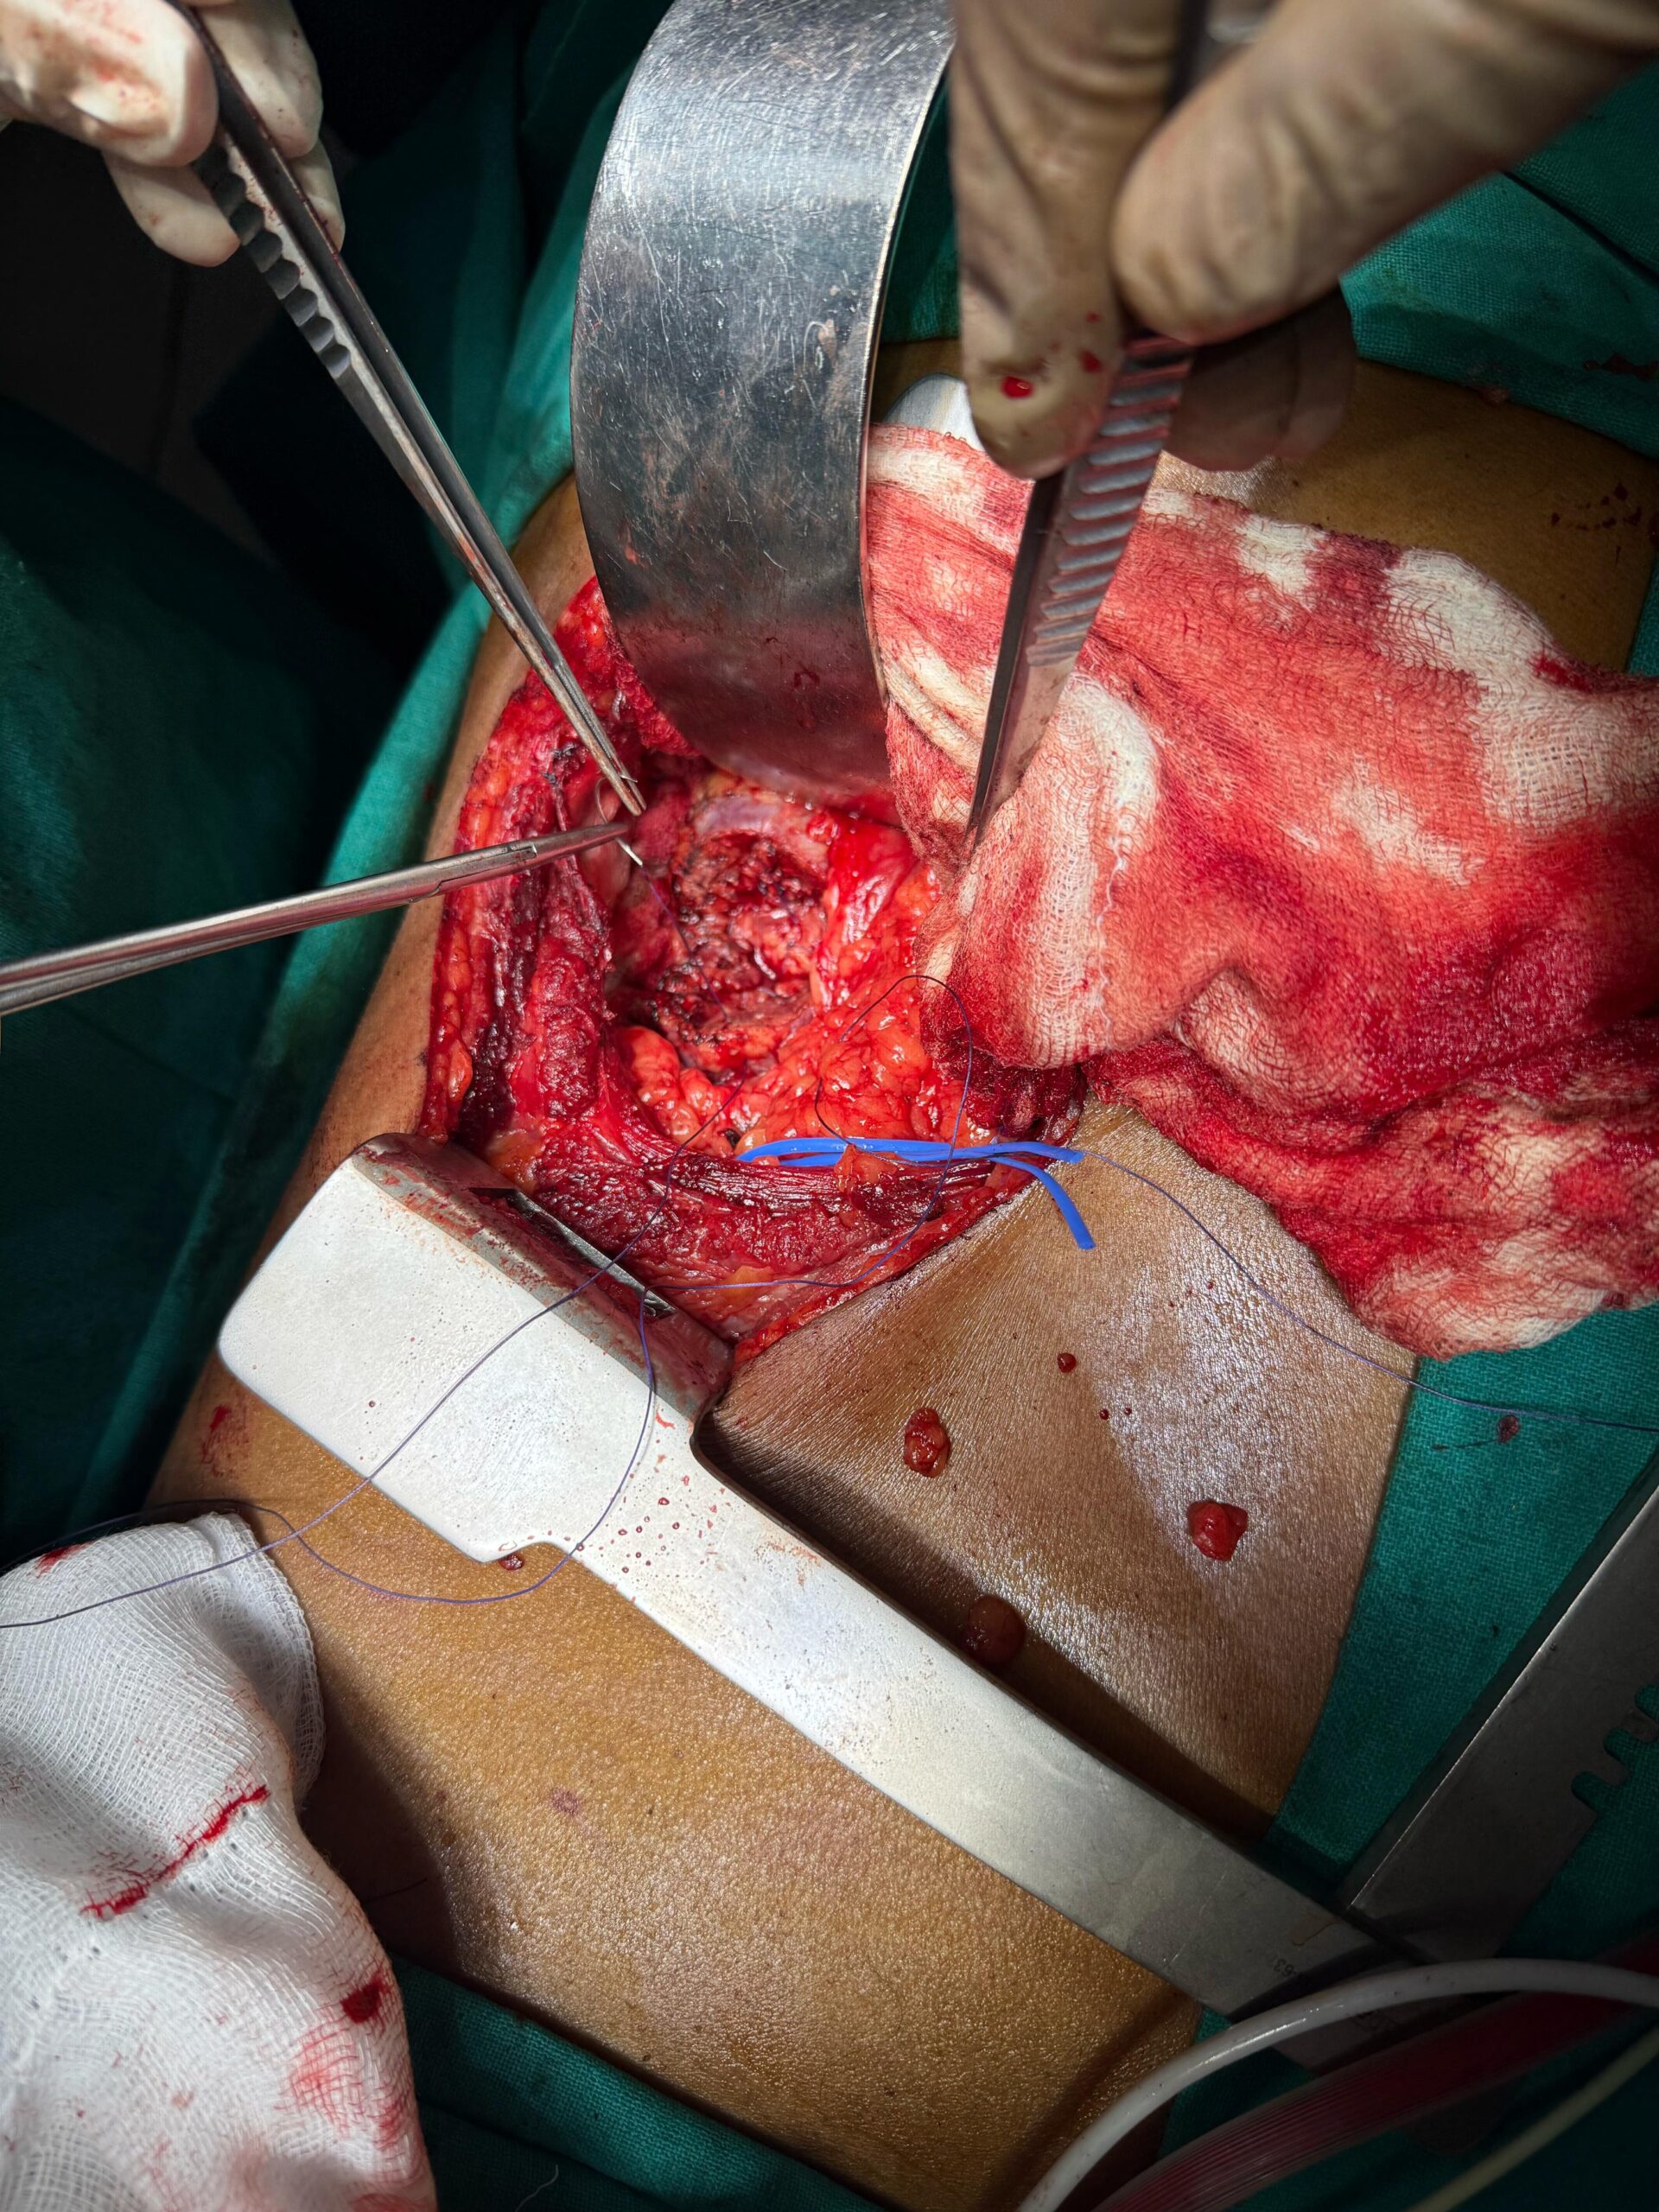

Our Gallery